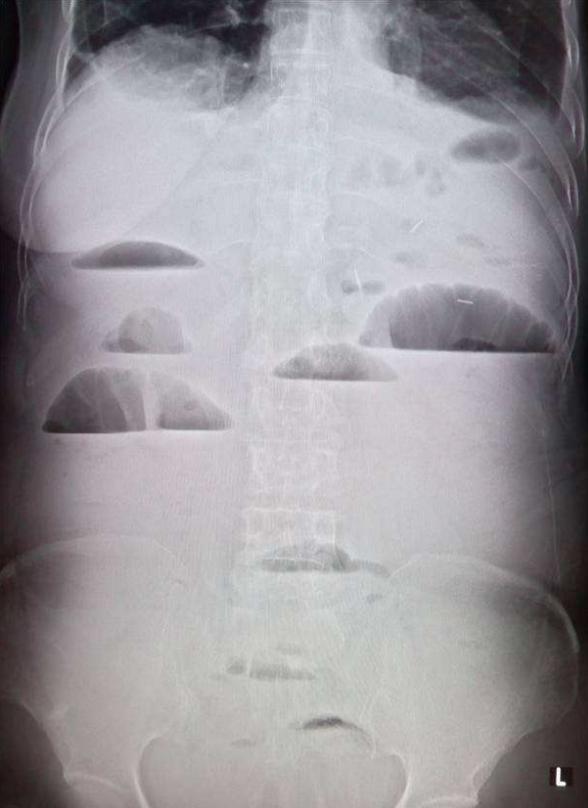

3.1.腹部平片

当腹部某种脏器因疾病而发生钙化或有不透X线的异物、结石,或腹腔内有游离气体出现,肠腔内气体、液体增多或肠管有扩张时,就会出现密度高低的差别而在照片上显示出来。异常结果:1.消化道肿瘤、炎症、外伤引起的消化道穿孔。2.肠梗阻,并可鉴别是机械性肠梗阻还是麻痹性或是绞窄性肠梗阻。3.可观察腹腔内脏器(肝肾脾等)的轮廓、位置和大小改变。例如肝脏肿瘤、包虫病、囊肿等病变可使肝脏轮廓发生改变,并且其体积可以增大。